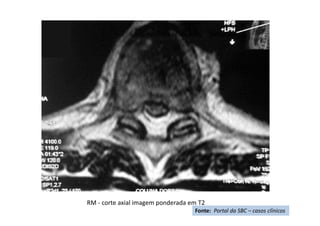

RM - corte axial imagem ponderada em T2

Fonte: Portal da SBC – casos clínicos